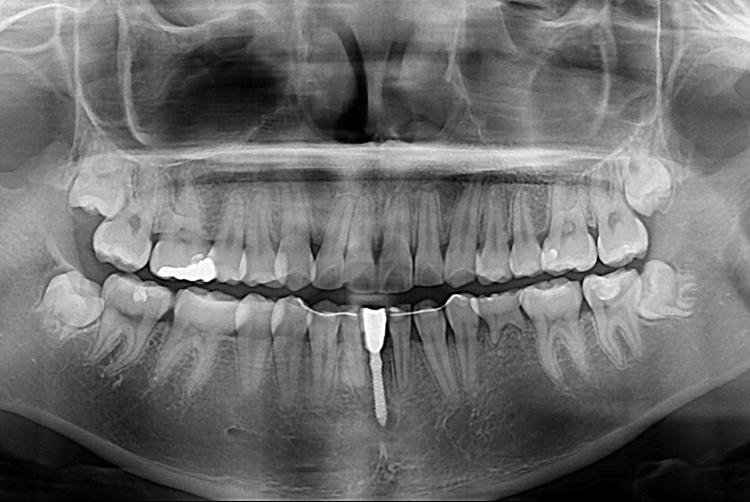

[임플란트] 앞니 임플란트

치료전 : 2019-06-11

세종치과는 많은 환자와 다양한 케이스를 바탕으로

항상 편안한 임플란트 수술을 제공하고자 노력하고,

오래동안 튼튼히 쓸 수 있는 임플란트 수술을 가장 큰 목표로 삼고 있습니다.